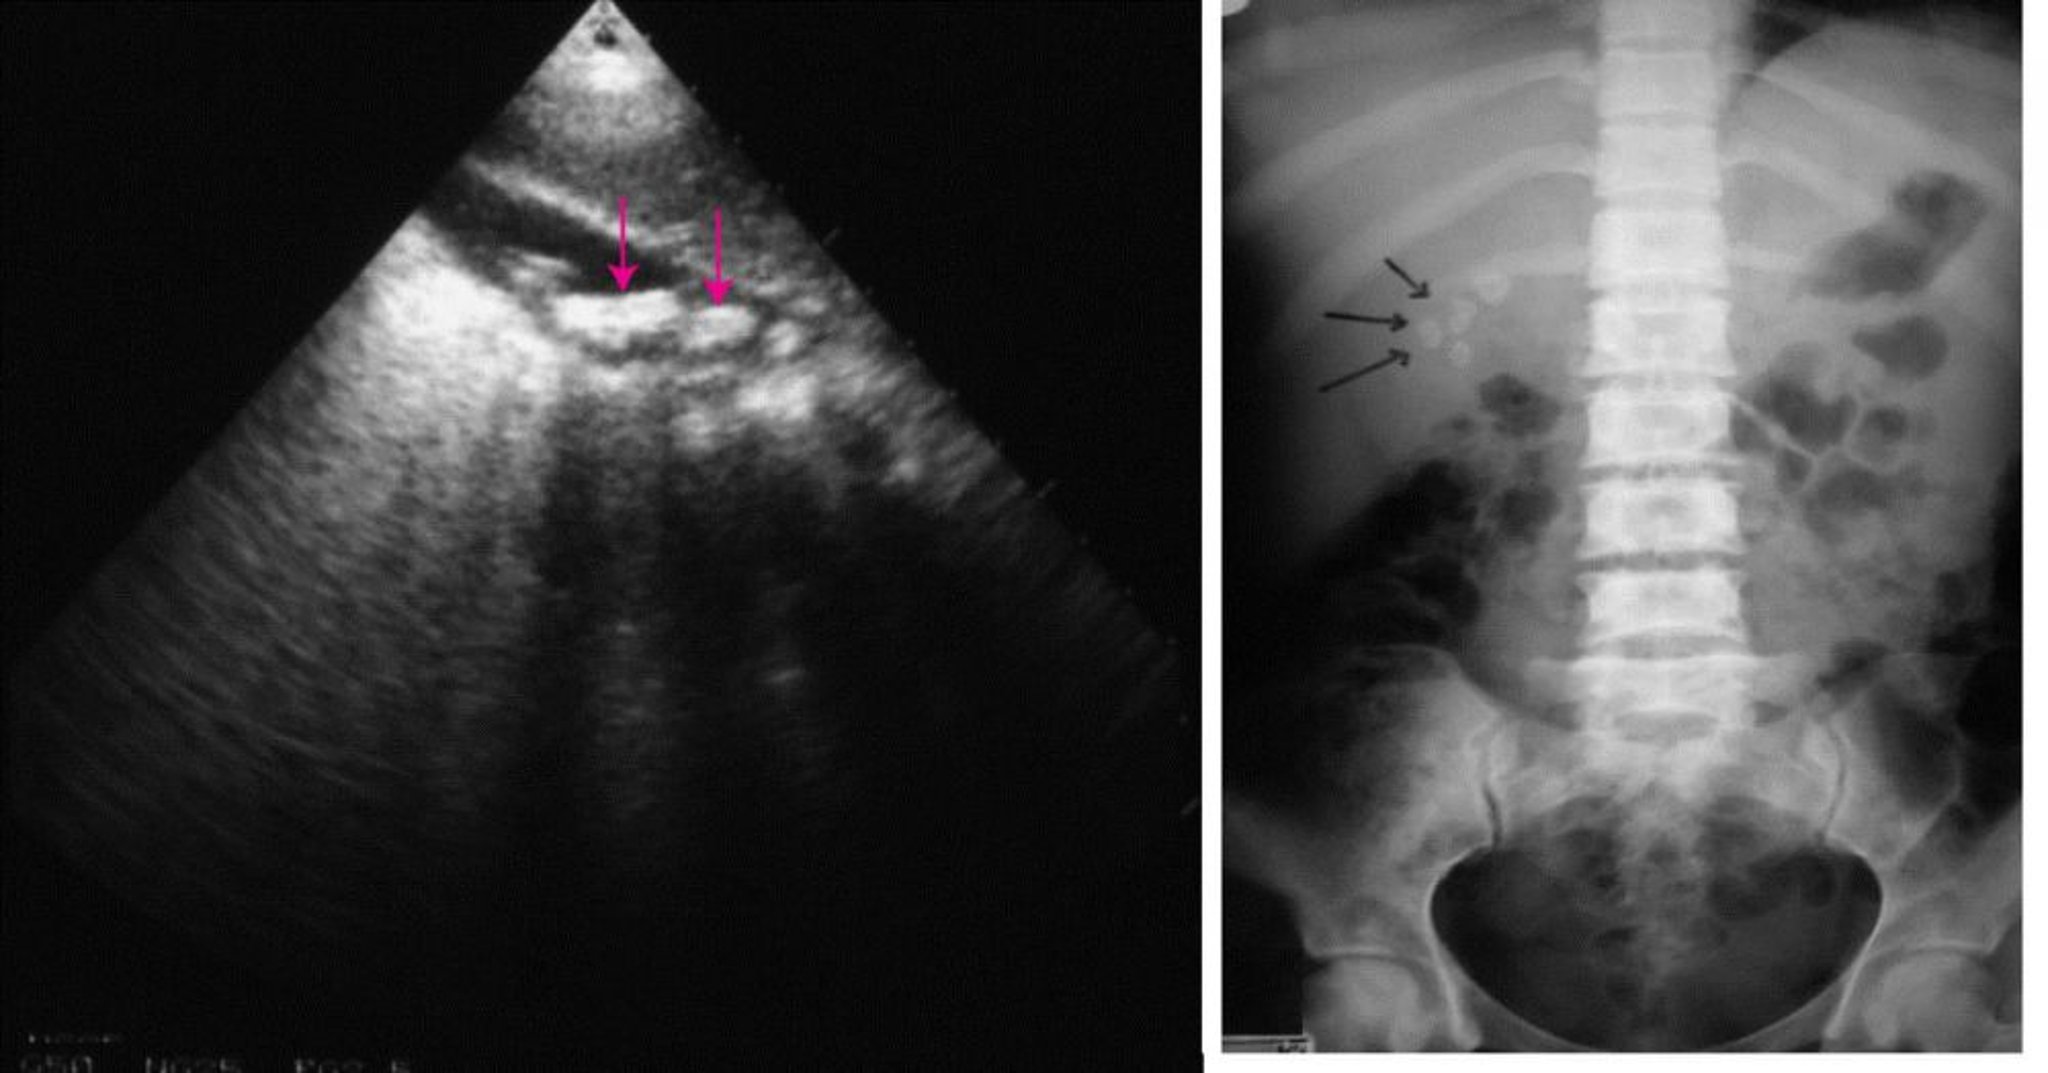

On the left, an abdominal ultrasound showing multiple gallstones (arrows). On the right, a plain abdominal radiograph showing radiopaque gallstones (arrows).

© Springer Science+Business Media